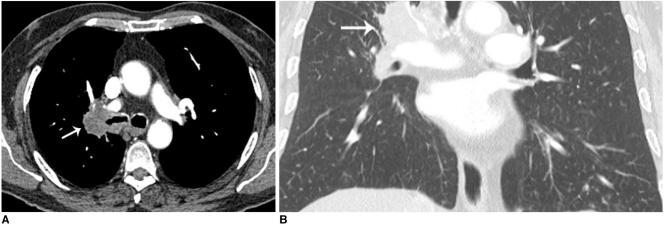

To evaluate the spectrum, prevalence, and significance of incidental non-cardiac findings (INCF) in patients referred for a non-invasive coronary angiography using a 128-slice multi-detector CT (MDCT).

The study subjects included 1,044 patients; 774 males (mean age, 59.9 years) and 270 females (mean age, 63 years), referred for a coronary CT angiography on a 128-slice MDCT scanner. The scans were acquired from the level of the carina to just below the diaphragm. To evaluate INCFs, images were reconstructed with a large field of view (> 300 mm) covering the entire thorax. Images were reviewed in the axial, coronal, and sagittal planes, using the mediastinal, lung, and bone windows. The INCFs were classified as severe, indeterminate, and mild, based on their clinical importance, and as thoracic or abdominal based on their locations.

Incidental non-cardiac findings were detected in 56% of patients (588 of 1,044), including 435 males (mean age, 65.6 years) and 153 females (mean age, 67.9 years). A total of 729 INCFs were observed: 459 (63%) mild (58% thoracic, 43% abdominal), 96 (13%) indeterminate (95% thoracic, 5% abdominal), and 174 (24%) severe (87% thoracic, 13% abdominal). The prevalence of severe INCFs was 15%. Two severe INCFs were histologically verified as lung cancers.

The 128-slice MDCT coronary angiography, in addition to cardiac imaging, can provide important information on the pathology of the chest and upper abdomen. The presence of severe INCFs is not rare, especially in the thorax. Therefore, all organs in the scan should be thoroughly evaluated in daily clinical practice.

评估使用 128 层多探测器 CT(MDCT)进行非侵入性冠状动脉造影检查的患者中偶然的非心脏发现(INCF)的谱、患病率和意义。

研究对象包括 1044 名患者;774 名男性(平均年龄 59.9 岁)和 270 名女性(平均年龄 63 岁),因冠状动脉 CT 血管造影而在 128 层 MDCT 扫描仪上接受检查。扫描范围从隆突到膈肌以下。为了评估 INCF,使用大视野(>300mm)重建图像,覆盖整个胸部。在轴位、冠状位和矢状位平面上,使用纵隔、肺和骨窗对图像进行了评估。根据其临床重要性,将 INCF 分为严重、不确定和轻度,并根据其位置分为胸部或腹部。

在 56%的患者(1044 名患者中的 588 名)中发现了偶然的非心脏发现,包括 435 名男性(平均年龄 65.6 岁)和 153 名女性(平均年龄 67.9 岁)。共观察到 729 例 INCF:459 例(63%)轻度(58%胸部,43%腹部),96 例(13%)不确定(95%胸部,5%腹部)和 174 例(24%)严重(87%胸部,13%腹部)。严重 INCF 的患病率为 15%。2 例严重 INCF 经组织学证实为肺癌。

128 层 MDCT 冠状动脉造影术除了心脏成像外,还可以提供有关胸部和上腹部病理学的重要信息。严重 INCF 的存在并不罕见,尤其是在胸部。因此,在日常临床实践中,应彻底评估扫描中的所有器官。